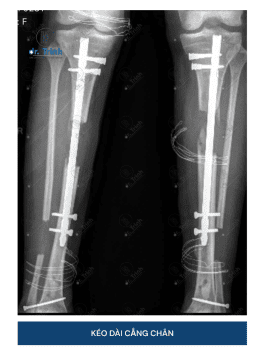

Xem thêmPHẪU THUẬT KÉO DÀI CHÂN – NÊN KÉO ĐÙI HAY KÉO CẲNG CHÂN?

Phẫu thuật kéo dài chân đã trở thành một giải pháp phổ biến cho những...